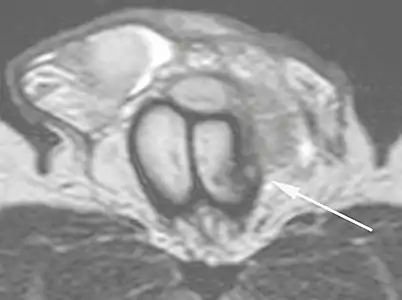

B: Axial T2-weighted turbo spin-echo magnetic resonance imaging scan showing left-sided discontinuity of the tunica albuginea (arrow), secondary to fracture.[2]